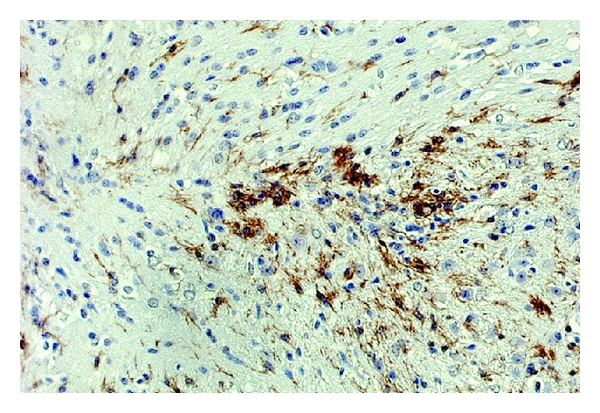

In animals stimulated with Ptx, the peak of cell infiltration occurred 6 days after infection, in correlation with OPN expression, and was followed by a gradual decay of the number of infiltrating cells. The characterization of the infiltrating cells by FACS, at 6 days, revealed a significant increase of CD45hi cells in the ipsilateral lobe of Ptx-injected animals, both in β-gal and in OPN-injected brains, but was especially marked in the OPN mice relative to the β-gal (Figure 1(f), , 2-way ANOVA followed by Bonferroni’s test). Importantly, the examination of the contralateral naïve hemisphere of the brains revealed that the focal expression of viral vector encoded products did not affect the BBB in a broad manner. Taking into account the injected lobes, the CD45hi-gated infiltrating immune cells in OPN-injected animals were predominantly CD11b+ (also CD11c-) macrophages (Figure 1(g)), but cells expressing T cell markers, CD3+CD4+ (Figure 1(h)) and CD3+CD8+ (Figure 1(i)), were also identified. The enrichment of macrophages in the brains of mice receiving the OPN vector and Ptx treatment was confirmed by immunohistochemistry for the detection of F4/80+ macrophages in the site of lesion (Figure 1(j)). Isotype controls were performed (Figure 1(k)). Cells with morphology of neutrophils or expressing CD11b+ Gr1high were not observed in the injection site. Many mechanisms for Ptx action have been proposed, such as increased BBB permeability and stimulation of leukocyte infiltration [31, 32, 34]. We hypothesized that Ptx-injected animals increased the expression of OPN receptor in peripheral immune cells, particularly in CD11b+ macrophages. Indeed, using flow cytometry on cells isolated from the peripheral sites, such as brain-draining deep cervical lymph nodes, we found that gated CD11b+ CD11c-Gr1low macrophages from Ptx-injected animals (red line) had increased expression of the CD44v6 isoform, when compared to animals injected with saline into the peritoneum (blue line) (Figure 1(l)).

Injection of the recombinant adenoviral vector encoding OPN into the caudoputamen of OPN-deficient mice, based on a previously described model [30], led to a localized expression of OPN (Figures 1(a) and 1(b)), and was restricted to the injection site (Figure 1(b)); similarly, the β-gal containing vector led to the expression of β-gal (data not shown). The accumulation of inflammatory cells in the nonperipherally activated OPN-injected ipsilateral injected or contralateral hemispheres (to control for leaks), or in comparison with the β-gal injected brains, 6 days after injection, was not significantly different, as measured by the expression of CD45hi-gated cells by FACS, which characterize infiltrating leukocytes of peripheral origin (Figure 1(f)). Iba1+ cells with morphological characteristics of activated microglia were more abundant in the site of OPN injection (Figure 1(c)) when compared to the site of β-gal injection (Figure 1(e)), as detectable by IHC. F4/80+ macrophages were localized adjacent to the OPN-expressing lesion site (Figure 1(d)), as determined by IHC, and their numbers were not different in comparison to β-gal-injected sites (Figure 1(g)). We also observed a local increase of GFAP+ astrocytes (not shown).